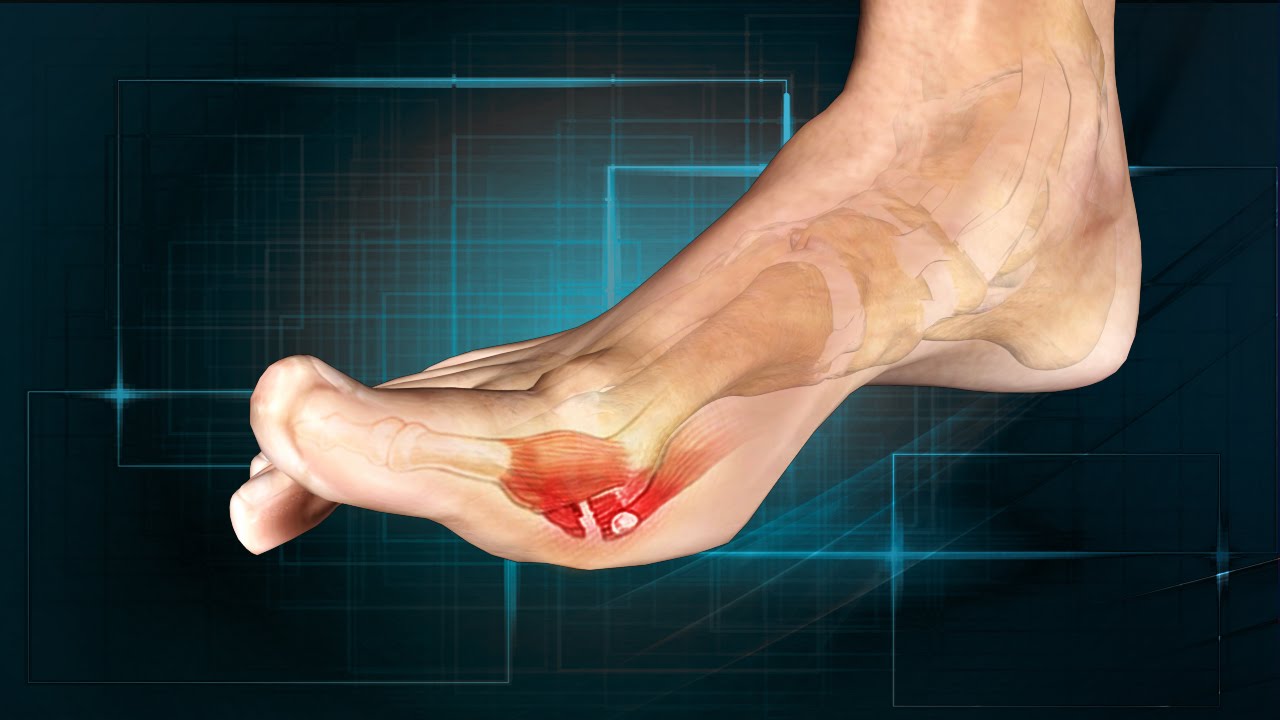

Plantar fasciitis mechanism (4)

Overuse, overweight, pregnant, improper footwear

Plantar fasciitis

Pain in bottom of foot by heel, pain decrease as foot warms, pain increases with standing/ PF

Heel spur treatment

Ice, NSAIDs, orthotics, night splints, stretching plantar fascia, cortisone shots, surgery

Night splint

Device that keeps plantar fascia in stretched position